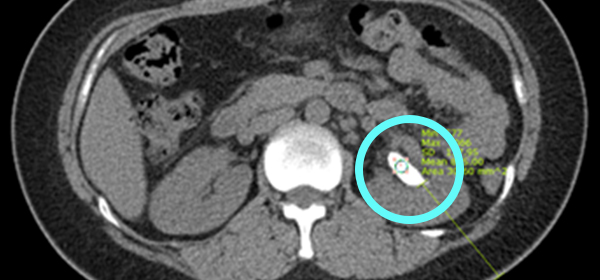

ÄÄÇ»ÅÍ´ÜÃþÃÔ¿µ (CT)